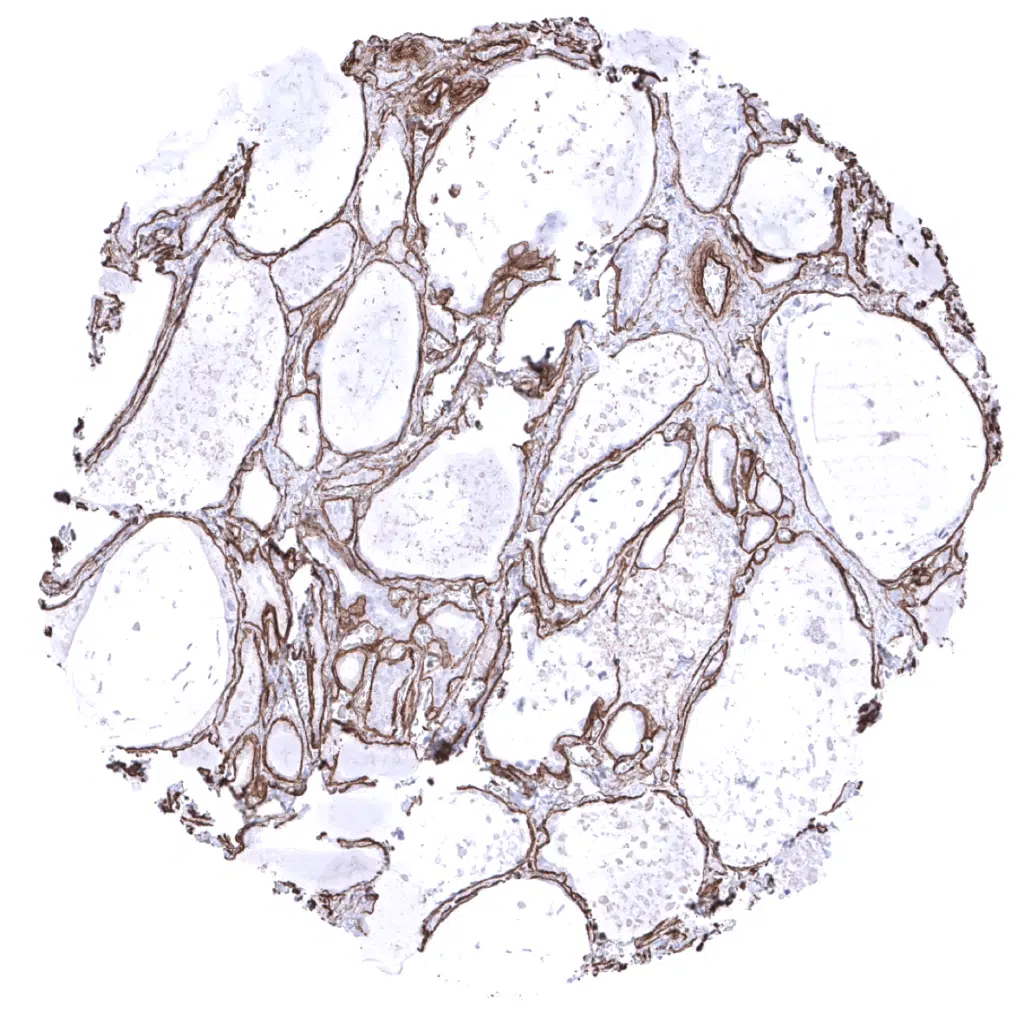

Fat - Each fat cell is surrounded by collagen IV.